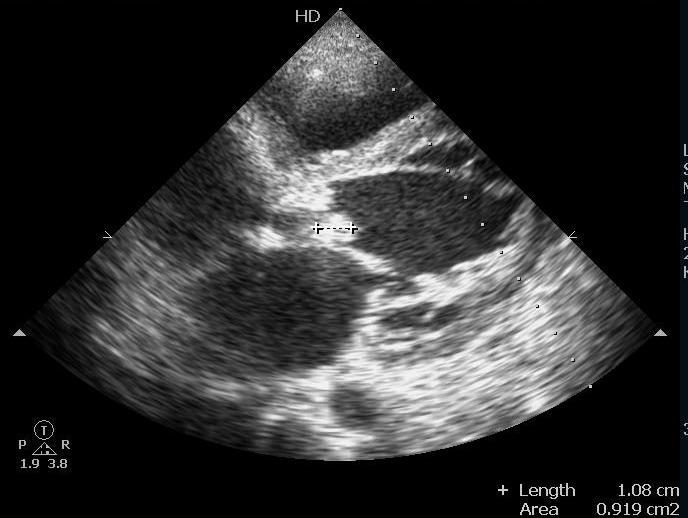

Женщина 39 лет поступила с болями в животе, абстинентным синдромом. При УЗИ брюшной полости признаков острого панкреатита не выявлено, определялись застойные изменения в печени двусторонний гидроторакс, небольшое количество жидкости в брюшной полости. Ни температуры ни признаков воспаления в анализах не было, а вот в сердце...

Инфекционный эндокардит, сочетанный аортальный порок- митральный стеноз, выраженный незначительно, аортальная недостаточность. Хочется увидеть ЦДК.

Но точно вегетации на аортальном клапане + недостаточность АК- инф.эндокардит.

Митрального стеноза при эхокардиографии небыло, а вот эндокардит с поражением аортального клапана на аутопсии подтвердился.

Прошу прощения, имел в виду аортальный стеноз, просто описался. Мысль об аортальном стенозе возникла на основании увеличения максимального систолического давления на аортальном клапане.